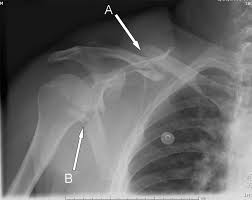

Clavicle Series Radiology Reference Article Radiopaedia Org

Clavicle Series Radiology Reference Article Radiopaedia Org from prod-images-static.radiopaedia.org

Outline • plain films different views • positioning • interpretation of the plain film. Bones • sternum • clavicles • scapulae • ribs • spine. The medial ends of the clavicles should be equidistant from the spinous process at the level of t4/ t5. Please remove all obscuring objects and, as always, practice proper radiation protection. Assessing the image quality, ripe mnemonic is used;